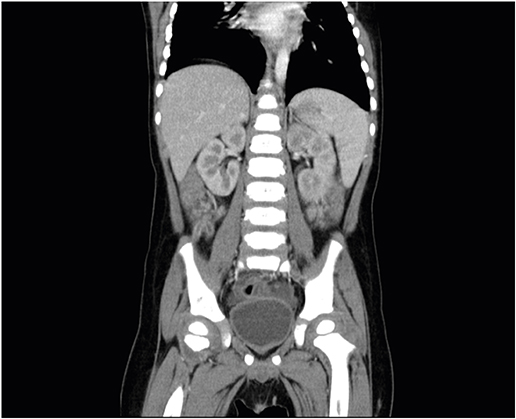

The patient was subjected to bowel sonography to exclude intussusception; with results showing no evidence of intussusception but edematous bowel wall thickening, which suggested enteritis, and a 6 mm dilatation of the appendix with wall thickening, which was suspicious of early appendicitis (Fig. 2). Intravenous antibiotics were initiated upon the suspicion of bacterial enteritis and symptomatic medication was administered for watery diarrhea and abdominal pain.

Fig. 2

Wall thickening with 6 mm of dilatation of appendix was observed on bowel sonography.